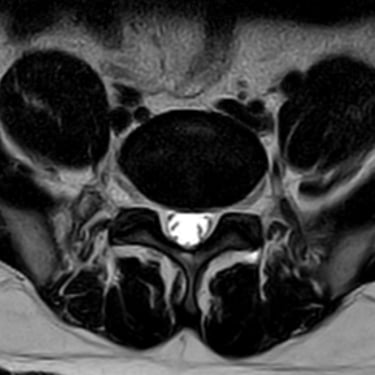

Discopatía Lumbar Degenerativa con Artrosis Facetaria | Diagnóstico por Resonancia Magnética

La discopatía lumbar degenerativa con artrosis facetaria es una causa frecuente de dolor lumbar crónico, que limita la movilidad y la calidad de vida del paciente. Esta condición combina la degeneración de los discos intervertebrales con el desgaste de las articulaciones facetarias, lo que puede generar inestabilidad y compresión nerviosa. La resonancia magnética (RMN) es la herramienta diagnóstica más precisa, ya que permite identificar deshidratación y colapso discal, hipertrofia facetaria, estenosis foraminal y signos de inflamación. El diagnóstico temprano es fundamental para establecer un tratamiento adecuado, que puede ir desde medidas conservadoras hasta técnicas quirúrgicas mínimamente invasivas.